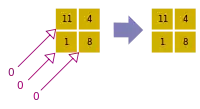

- A basic premise in back-projection is that any attenuation of the X-ray beam has occurred uniformly along the path followed from the source to the detector. Let's consider a simple tomographic slice containing just four voxels to illustrate the computational approach - see Figure 7.11. The first projection, P1 is obtained from a horizontal exposure from left to right in the figure. The back-projection of P1 involves putting the values 7 and 9 in both elements of the first and second rows, respectively. The second projection, P2 adds a 4 to the top right element, 1 to the bottom left element and 11 to the other two elements when it is back-projected. The other projections are treated in a similar fashion. Following regularisation of the data set the final image is obtained at the bottom left of the figure.

- The first estimate of the image matrix is made by distributing the first projection, P1, evenly through an empty pixel matrix. The second projection, P2, is then compared to the same projection from the estimated matrix and the difference between actual and estimated projections is added to the estimated matrix. The process is repeated for all other projections.